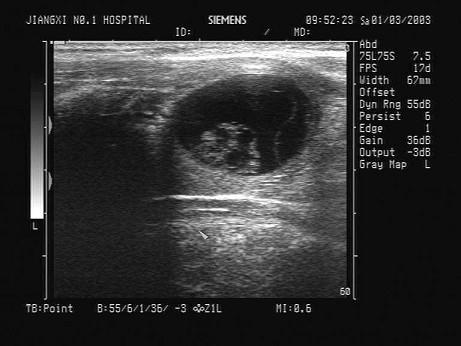

问题 患者发现颈部无痛性肿块数年。甲状腺超声见左侧甲状腺一肿块,如图。最可能的诊断为?(?)

选项 A.甲状腺癌 B.结节性甲状腺肿 C.甲状腺炎 D.甲状腺囊腺瘤 E.甲状腺囊肿

答案 D